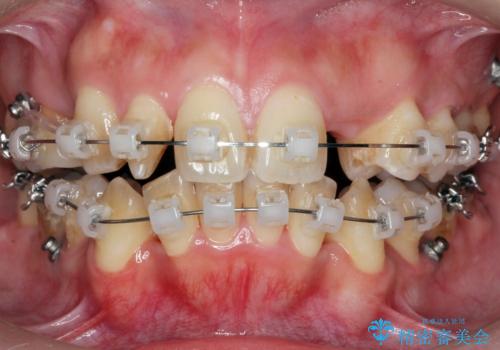

重度のがたつき 矯正治療+セラミック治療で綺麗な歯並びに 矯正専門では難しい治療

- ワイヤー矯正

- 歯並びを気にして来院。

乳歯が残存しており、また左上の犬歯もずれて生えてきていました。

右上の前歯も細長い特殊な形をしていました。(矮小歯といいます)